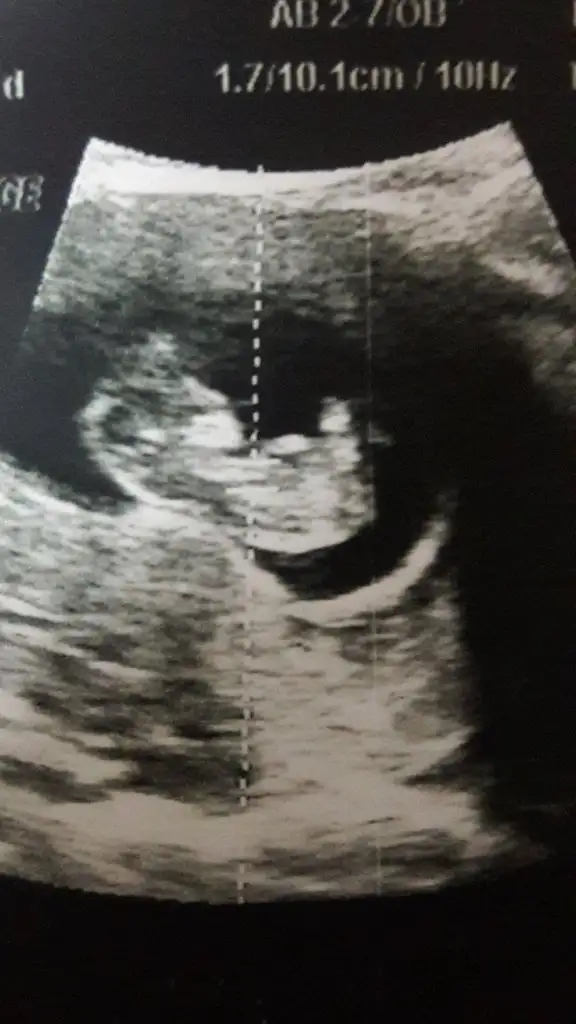

Erkek nub görunmuyor kafa yapısınagöre dedim tutmayabilir şu an kaç haftalıksınız dr 12 haftasındamı dedi kızKızlar doktorum bir türlü emin olamıyor çıldıracağımkıza benziyor ama kıyafet alma dedi, bir daha bakın şuna lütfeen 12 hafta 1 günlük burda

12 hafta 1 günlükken tahminim kız dedi.emin olamadı tam.bna da çıkıntı gitmis gbi geldi ama siz dha iyi anlıyorsunuzErkek nub görunmuyor kafa yapısınagöre dedim tutmayabilir şu an kaç haftalıksınız dr 12 haftasındamı dedi kız

Kızım mı olacak yanikız gibi herhangi bir çıkıntı yok